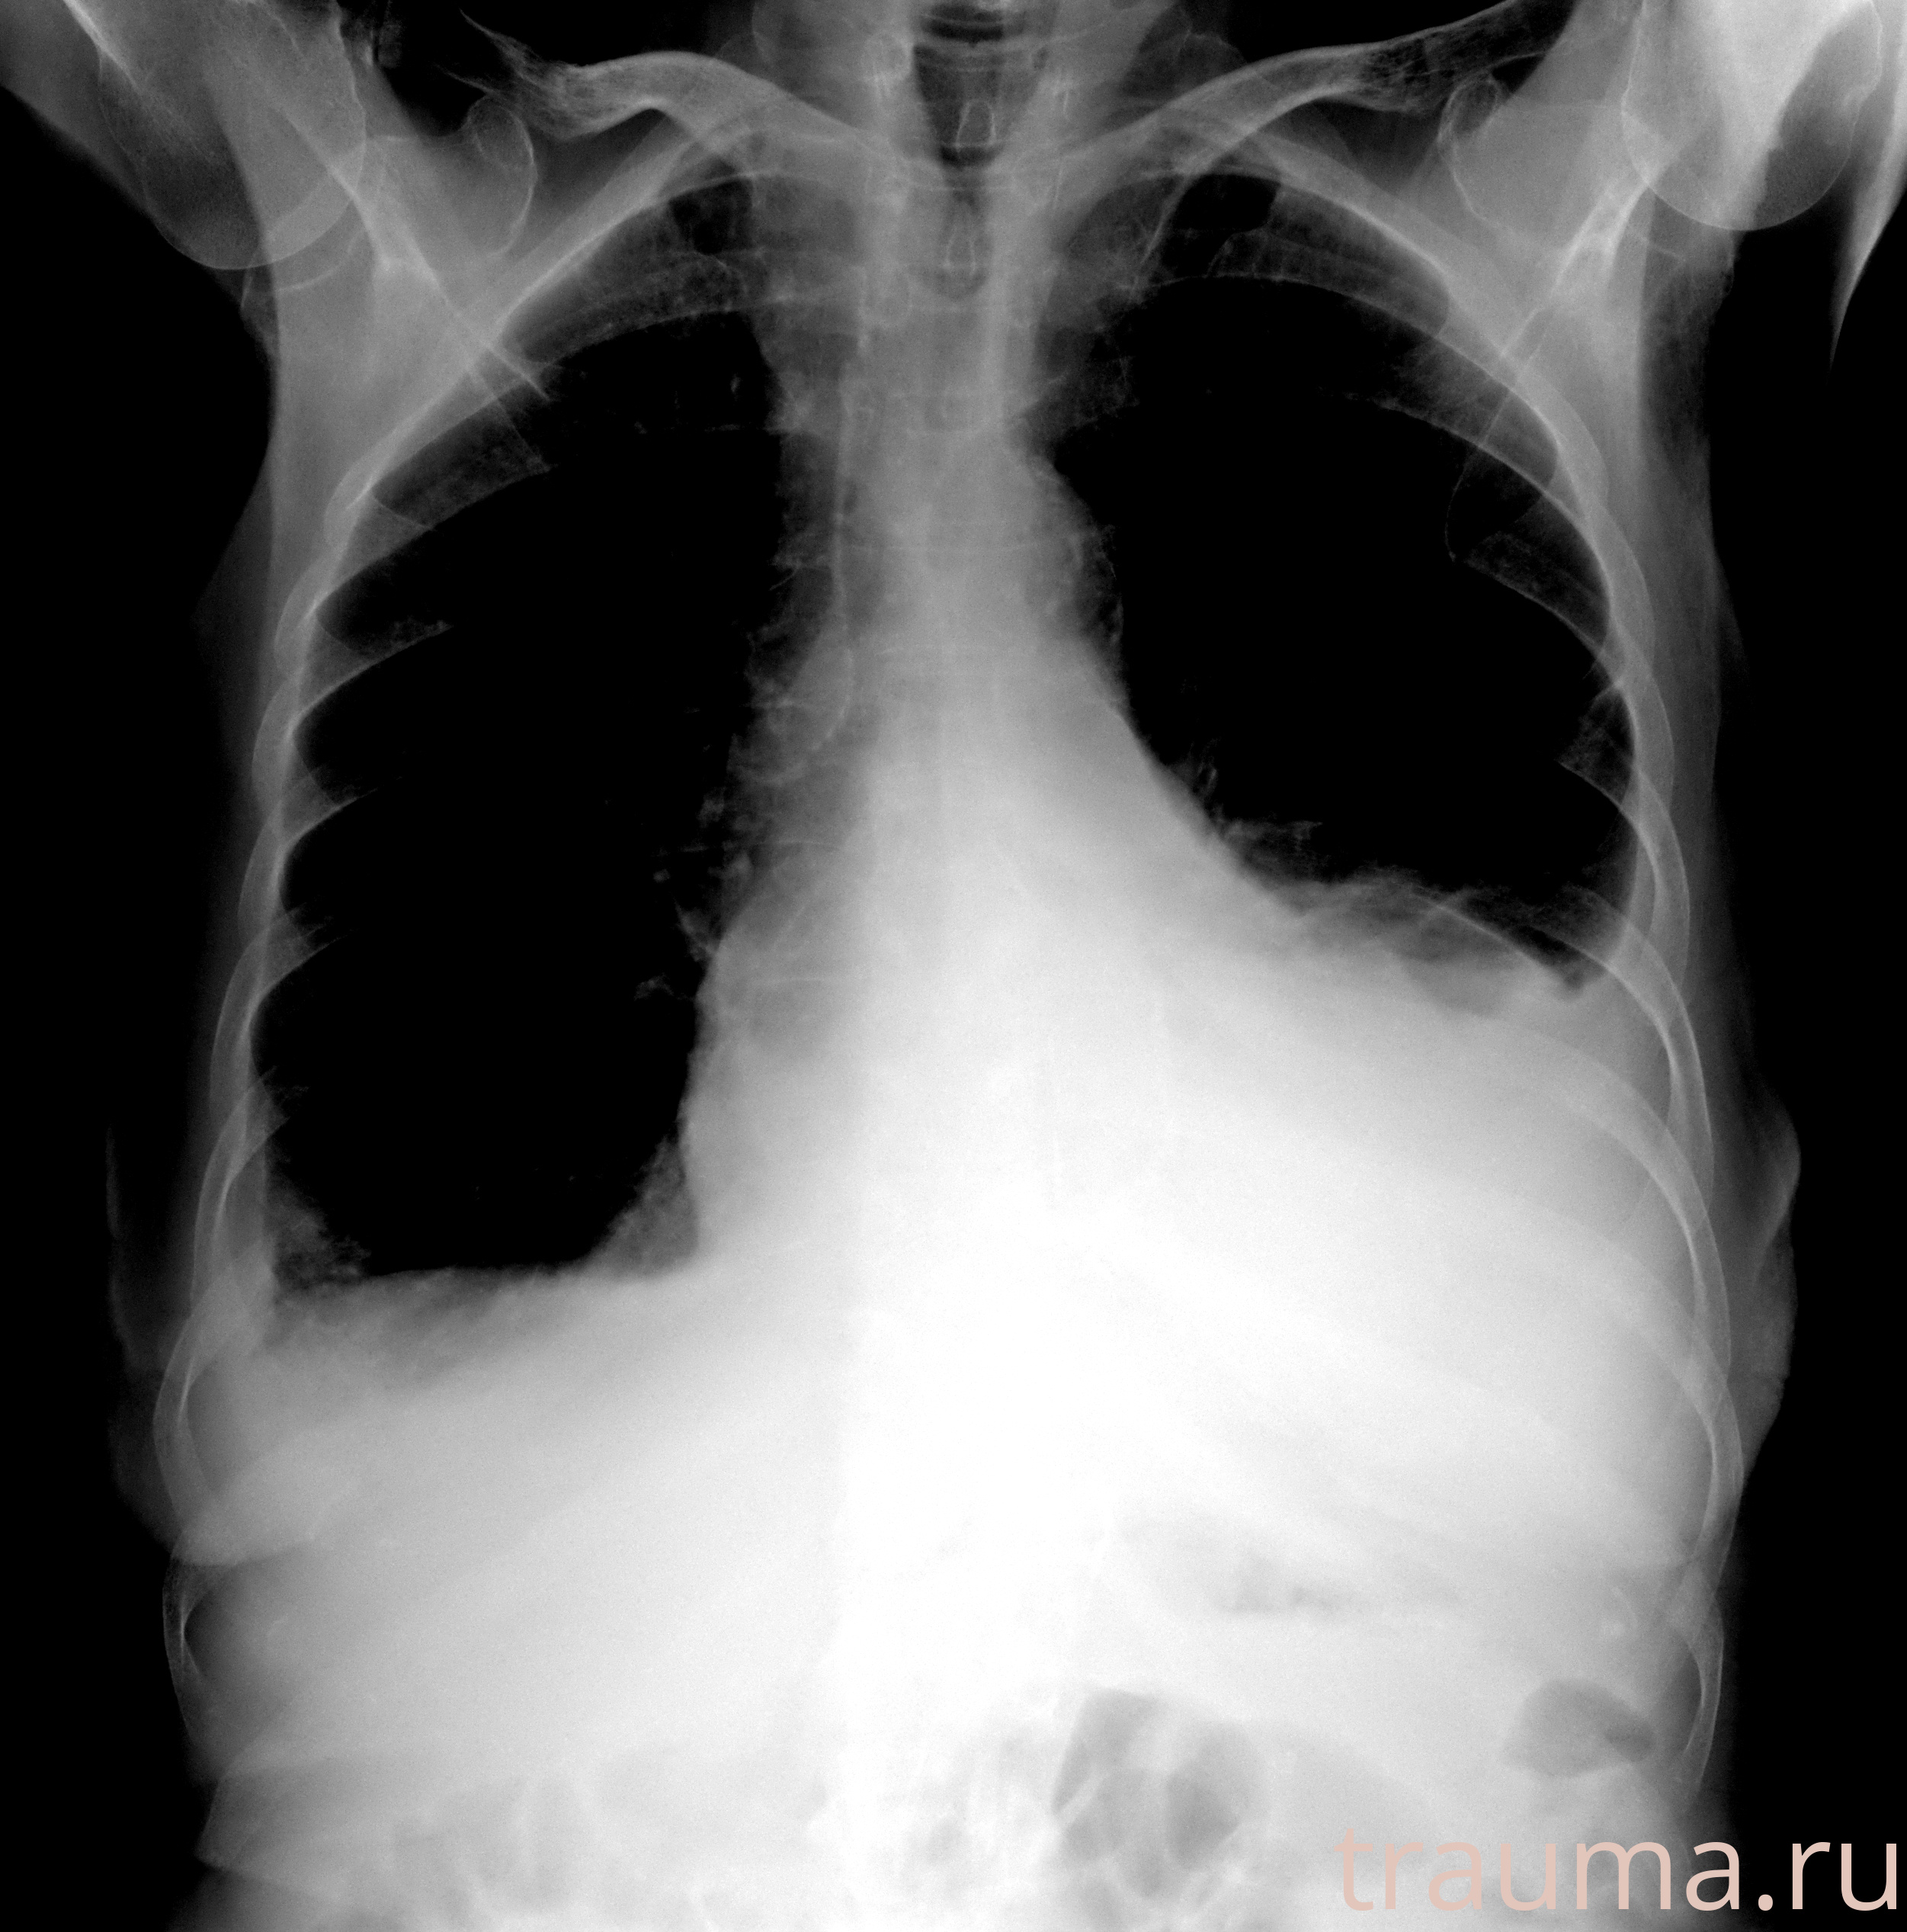

Рентген на дому: по вашему адресу приезжает врач-рентгенолог, травматолог-ортопед с мобильным рентгеновским аппаратом, проводит диагностику травмы или заболевания, делает необходимые рентгенограммы, дает рекомендации по дальнейшему лечению. Получить качественные снимки в домашних условиях возможно благодаря уникальной методике, разработанной МосРентген Центром для института  Склифосовского